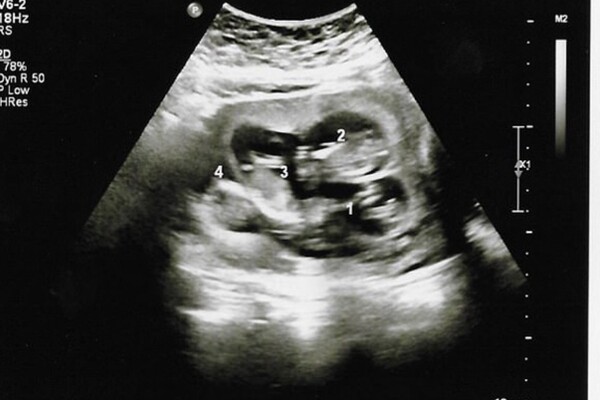

Nhưng “bất ngờ” dường như vẫn chưa chịu dừng lại. Đến tuần thai thứ 13, trong một buổi siêu âm định kỳ, bác sĩ tiếp tục thông báo còn một em bé khác đang phát triển trong bụng Danielle. Lúc này, cặp đôi chính thức biết mình đang mang thai 4, một trường hợp cực kỳ hiếm gặp, đặc biệt là khi thụ thai hoàn toàn tự nhiên.

Theo các chuyên gia, khả năng mang thai 4 tự nhiên chỉ rơi vào khoảng 1/700.000. Đáng chú ý hơn, bốn thai nhi của Danielle không phải là kết quả của trứng đã thụ tinh tách đôi (như sinh đôi cùng trứng), mà là từ bốn trứng riêng biệt, được thụ tinh bởi bốn tinh trùng khác nhau. Điều này khiến trường hợp của cô càng trở nên đặc biệt.

Các bác sĩ cho biết, việc “bỏ sót” thai nhi trong những lần siêu âm trước có thể do vị trí của em bé bị che khuất, chẳng hạn như nằm sau dây rốn hoặc các cấu trúc khác trong tử cung. Chính vì vậy, phải đến lần siêu âm thứ ba, toàn bộ bốn thai nhi mới được phát hiện đầy đủ.